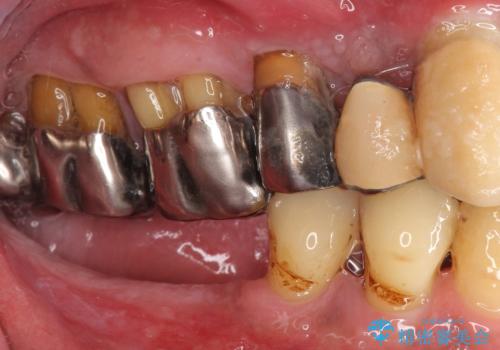

精査したところ、全顎的な重度の歯周病により右下の小臼歯(右下4)激しい動揺を認めました。

できるだけ自分の歯を残したいという患者様の強いご希望により、禁煙指導後再生療法(骨を増やす手術))を行いました。

再生療法から1年後リエントリー手術により骨の再生を確認し、骨外科処置(骨を平らにして歯周ポケットの根本的な改善を図る処置)を行ったのち、連結補綴を行いました。